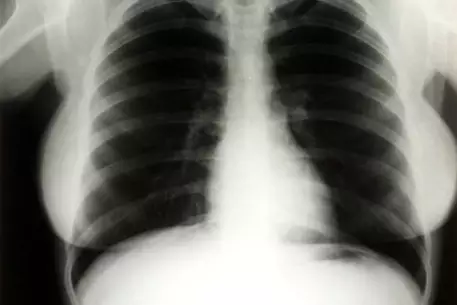

В казино "Планета Голливуд" в Лас-Вегасе пройдет аукцион, на котором будут представлены личные вещи знаменитой актрисы Мерилин Монро, пишет Daily Mail. Торги пройдут 26-27 июня этого года. На аукционе Julien's будет выставлен рентгеновский снимок Монро, сделанный в 1954 году, когда актриса была госпитализирована в больницу Cedars of Lebanon Hospital во Флориде с диагнозом эндометриоз. В то время она еще была замужем за бейсболистом Джо ДиМаджио (Joe DiMaggio). Об этом свидетельствует фамилия в подписи. Рентгеновские снимки актрисы долгое время служили учебным пособием для студентов медицинского университета. Начальная стоимость флюорографии составила более 1200 долларов. Также на торгах будут представлены запакованный флакон духов Chanel №5, ранее принадлежавший актрисе, деревянные лыжи с инициалами "ММ". Поклонники Монро также смогут приобрести стул, обитый зеленым бархатом. Сидя на нем, актриса позировала во время своей последней фотосессии для журнала Life незадолго до смерти в 1962 году. Начальная цена стула составляет 4000 долларов. Напомним, что выставленное на продажу место в склепе рядом с Монро на Мемориальном кладбище Вествуда в Лос-Анджелесе было куплено в августе 2009 года за 4,6 миллиона долларов.